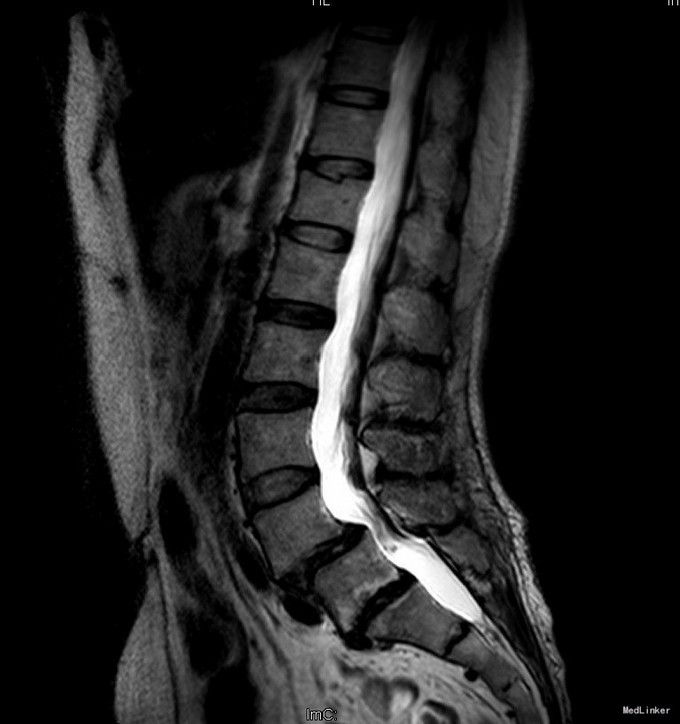

主诉:反复腰部疼痛20+年,加重伴双下肢胀痛麻木 现病史:患者于20+年前,因车祸行腰椎检查发现腰4椎体I°滑脱,并感腰部阵发性隐痛不适,一直未行特殊处理、4月前患者感腰部疼痛有所加重,并感双下肢阵发性胀痛麻木,久坐或弯腰后症状加重,以左下肢为甚,症状明显时难以直立行走,不伴畏寒发热、潮热盗汗等不适。10+天前患者在院外行理疗(具体不详),上述症状略有好转。在院外行腰椎x光摄片诊断为"腰4椎体II°滑脱,腰5椎体I°滑脱",故来我院就诊,门诊以"腰椎滑脱"收入住院

查体:脊柱外观无侧弯后突畸形,双下肢无肌肉萎缩。腰4-5、腰5骶1棘上棘旁轻压痛,伴左侧下肢放射;会阴部感觉未见异常,双侧小腿前外侧及足背足底感觉减退。腰椎前屈后伸及侧屈活动度正常;双下肢髂腰肌肌力4级,左侧直腿抬高试验阳性,加强试验阳性,左侧膝腱反射减弱,双侧病理征未引出。 辅助检查:院外腰椎正侧位片:腰4椎体II°滑脱,腰5椎体I°滑脱。

诊断:腰4椎II°滑脱症,腰5椎I°滑脱症 治疗:经后路腰4、5椎切开复位、椎管减压、Capstone椎间及后外侧人工骨+自体骨植骨融合、Legacy内固定术